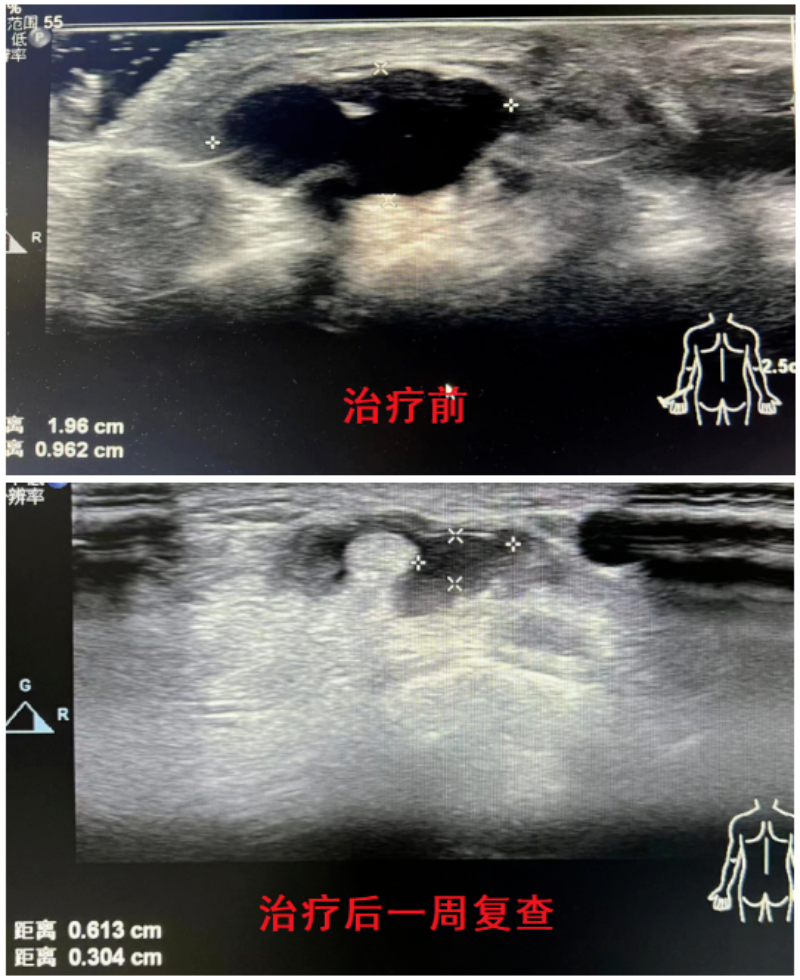

腱鞘囊腫不想開刀怎么辦?超聲引導下臭氧注射治療來解決!

近日我院來了一位患者,發現手腕背側囊腫半年余,近期伴有手腕酸脹不適。在超聲引導下精準穿刺囊腔,抽吸出淡黃色膠凍狀囊液,局部壓迫癥狀即刻得到緩解,受到患者及家屬的好評。

超聲引導下臭氧治療腱鞘囊腫能精準穿刺,可以安全避開血管、神經等重要組織臟器,行抽吸及藥物注射治療。相比傳統外科手術治療,具有微創、便捷、高效且費用低等優點,無需住院門診即可快速處理。抽吸注射治療與手術治療的復發率幾乎相當,可以替代大部分外科手術治療。